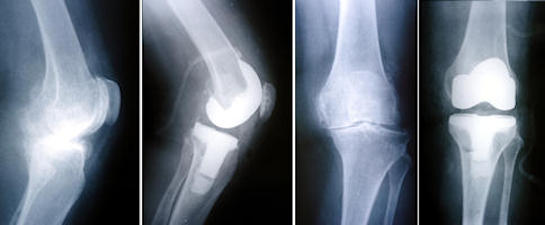

Total diz protezi nedir

Total diz protezi, aşınmış olan eklem yüzlerinin, metal ve polietilenden imal edilen, ağrısız eklem hareketi için tasarlanmış özel parçalar ile kaplanarak yapay bir eklem oluşturulmasıdır. İlk kez 1968 yılında uygulanan diz protezi, cerrahi teknikler, kullanılan maddeler ve tasarım alanındaki ilerlemeler sayesinde geliştirilerek günümüzde çok daha başarılı bir tedavi yöntemi olmuştur.

Kısmi (unikondiler) diz protezleri

Kısmi (parsiyel, unikondiler) diz protezleri, aşınmış olan diz ekleminin sadece bir kısmının protez ile yüzey kaplanmasının yapıldığı protezlerdir. Metal iki yüzey arasında plastik ara-parçadan oluşurlar. Cerrahın tercihine göre bu plastik ara parça hareketli veya sabit olabilir. Dizin iç ve dış yarısı için farklı tasarımları vardır. Eklemdeki aşınması dizin sadece sınırlı bir bölgesinde olan hastalarda unikondiler protezler tercih edilebilir.